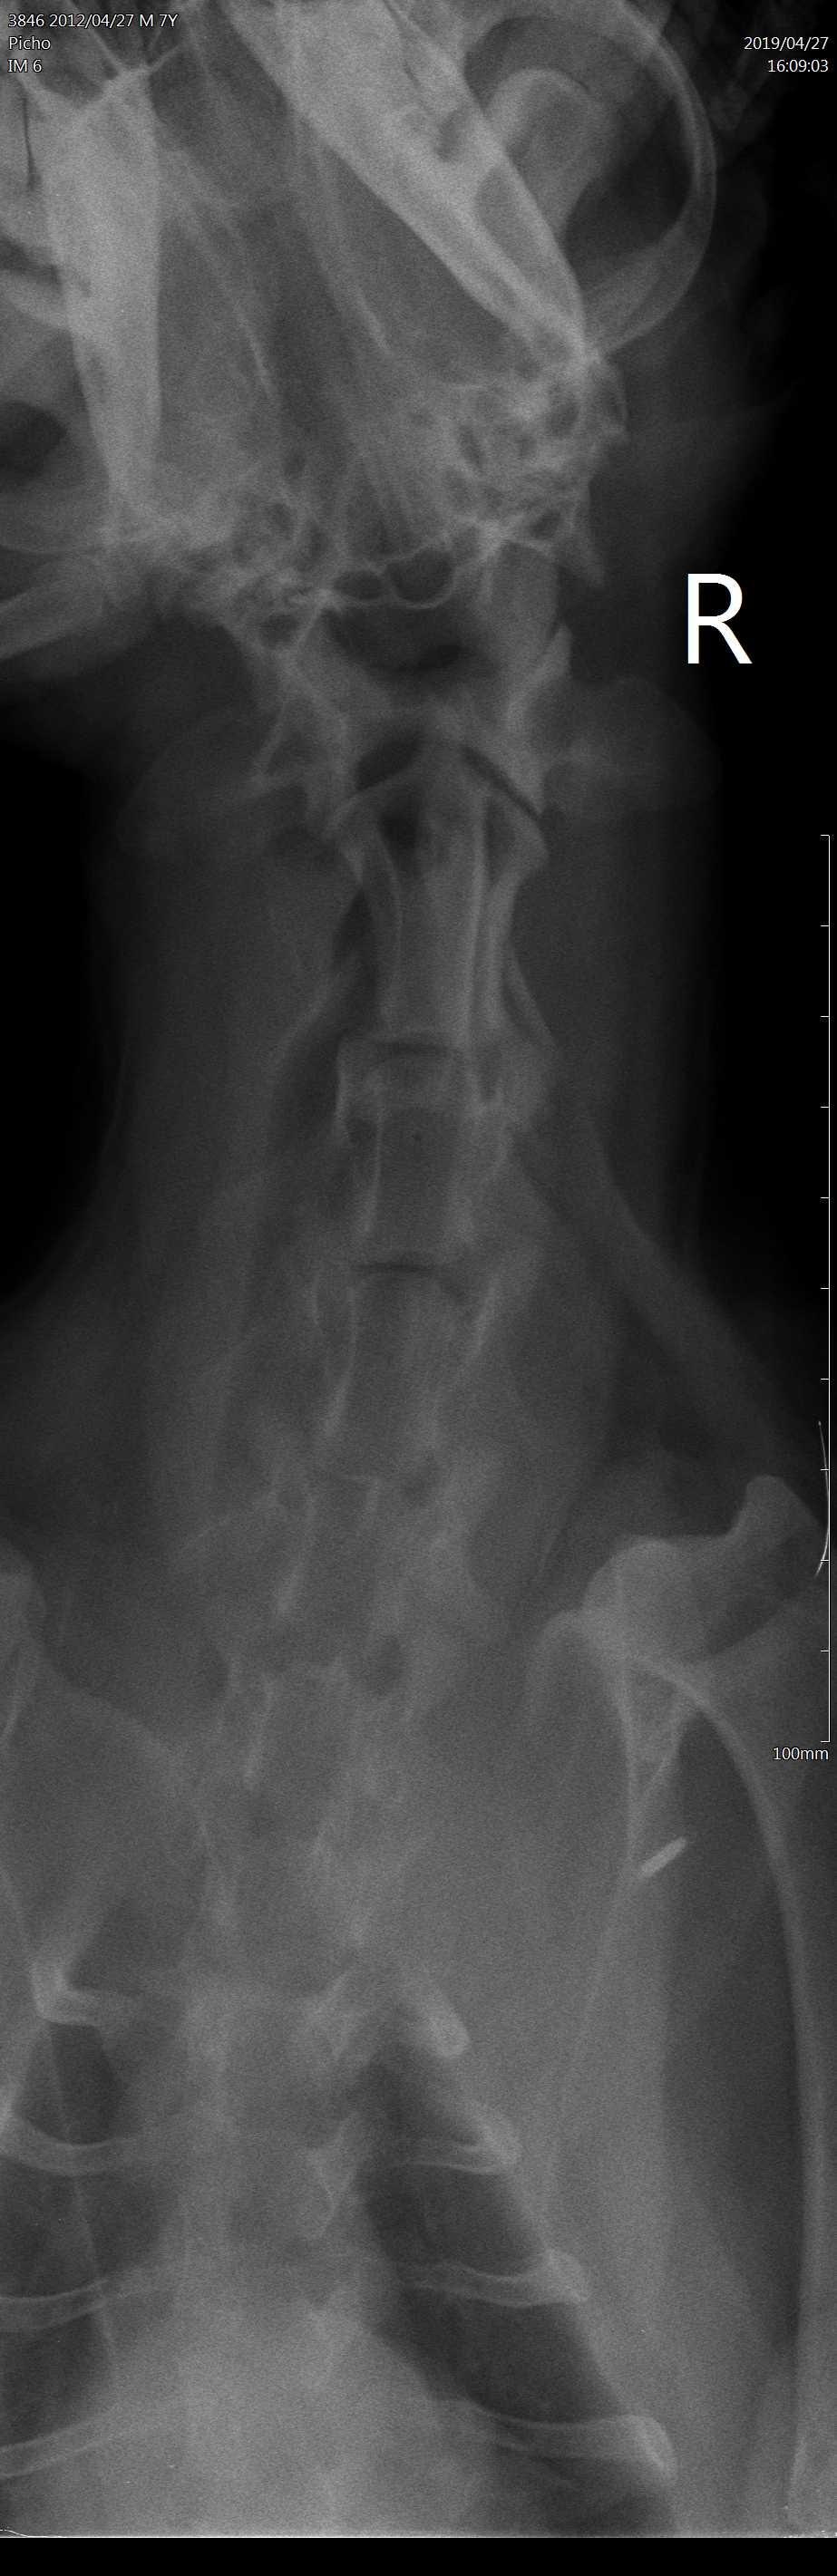

Dears, My dog had a seizure 1 month ago, 2 days ago he was vomiting. Then he was playing with my daughter and she accidentally hit him somewhere in the neck as she says, in the morning we found him paralysed with all legs he can't walk. We had an X-ray, attached see pics, our vet says he has a fluid between neck and spine that causes brain compression and he needs surgery. Please advise, my daughter is nervous she thinks that it is because of her, could this be the reason?

I hardly think your daughter could have hit Pich hard enough to cause this. It is more likely that this condition was underlying already especially with the history of a seizure. The x-rays are difficult to assess on this forum - when we try to enlarge them they get very grainy so I cannot comment on that part. Hope this helps. Best wishes.

I remember this question from before. There is no way your daughter hit this dog hard enough to cause paralysis unless she ran him over in a car or hit him with a baseball bat. Regardless, of whether she did or didn't cause it Pich needs surgery. I see the fluid your vet has noted. Your only options are to do the surgery or humane euthanasia - you cannot let him suffer like this. This has already been going on for weeks. Please do the surgery or relieve his suffering. I'm sorry you are going through this but you need to do what is best for Pich.